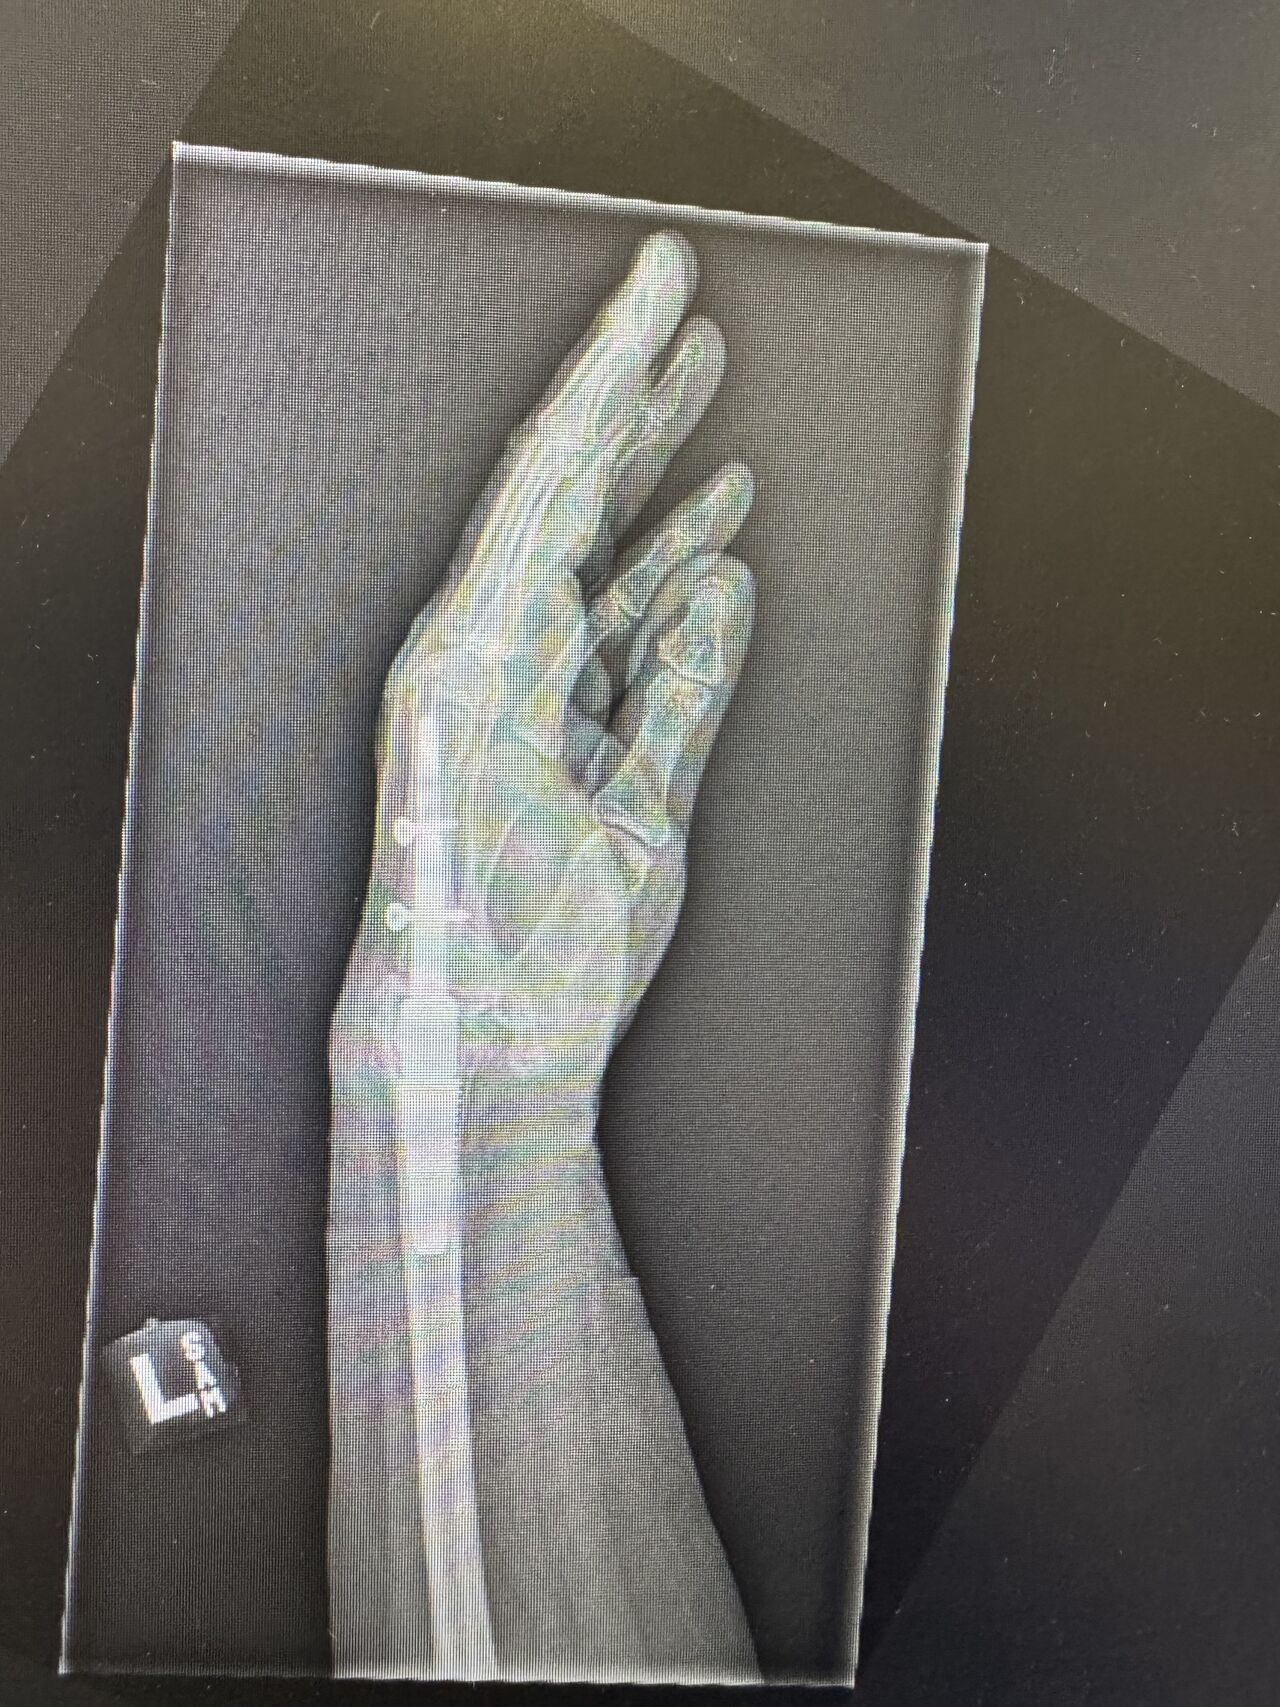

This challenging wrist reconstruction required a combination of advanced surgical techniques and careful multidisciplinary thinking:

• Deformity correction, drawing on Dr Sarah’s paediatric upper limb experience

• Use of the MotecWrist internal fusion system, keeping hardware within the wrist to minimise skin and tendon irritation

The outcome was a functional, sensate, and cosmetically acceptable hand—and, most importantly, a very happy patient.